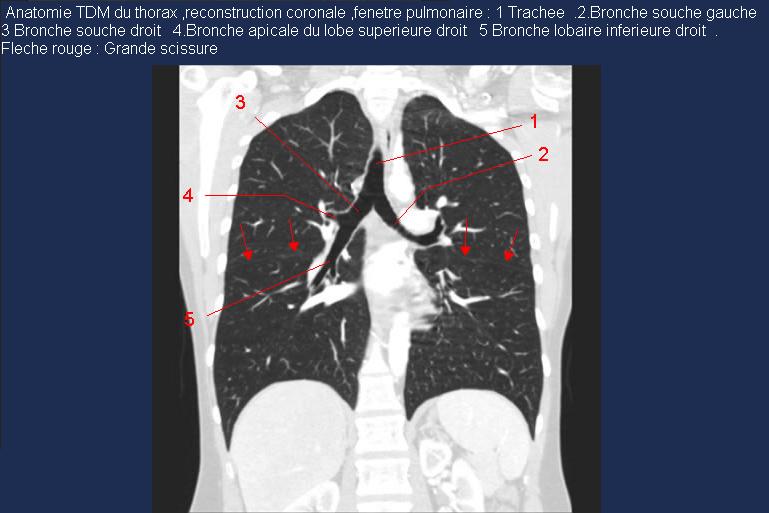

Image radiologique TDM normal , coupe

coronal , fenetre parenchymateuse du bronchous droit

et gauche . Le trachee et le bronchus droit et

gauche est en vue très nette hypodense sur ce

coupe. (

click pour entrer ) |